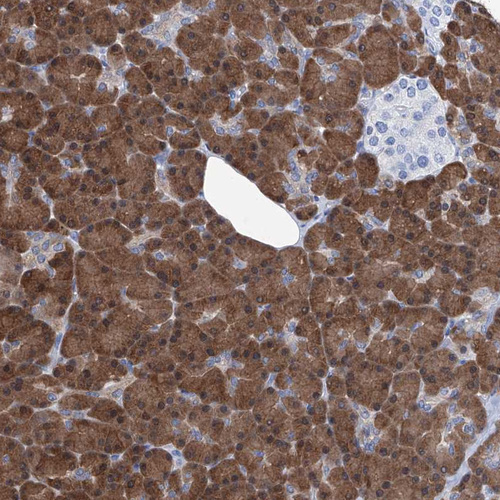

Immunohistochemical staining of human pancreas shows strong cytoplasmic positivity in exocrine glandular cells.